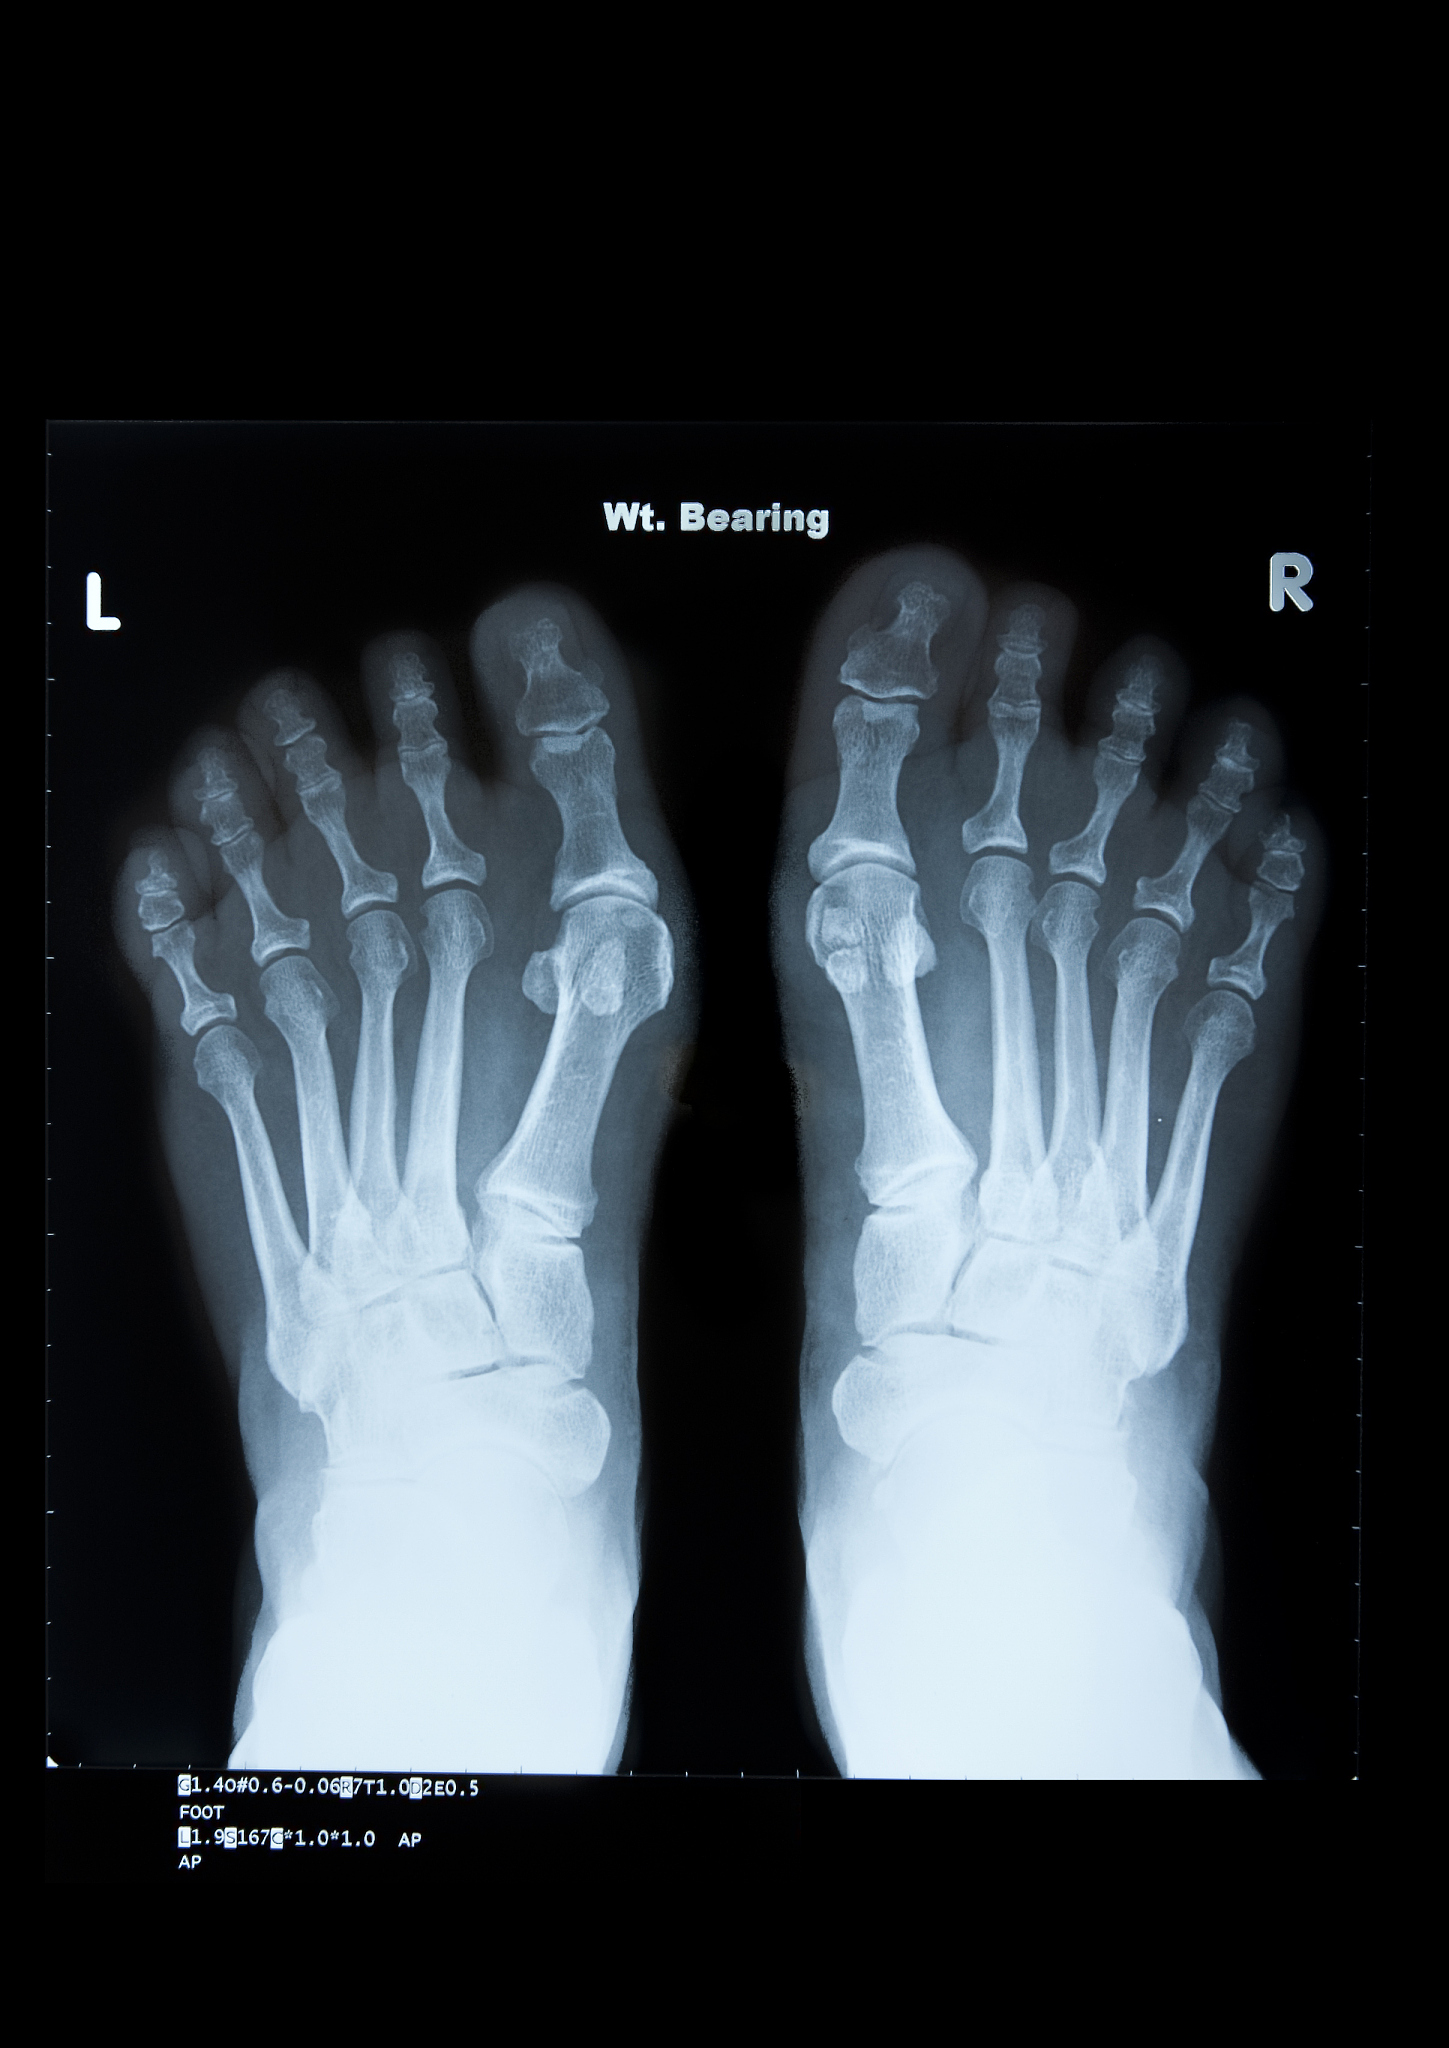

osteoidosis是一种罕见的骨病,也称为骨样物质沉积症。它是由于骨样物质在骨骼中异常沉积而引起的。这种疾病通常会导致骨骼中出现类似骨折的症状,但实际上并没有真正的骨折发生。与骨折不同,osteoidosis的症状通常会自行消失,而无需进行手术治疗。然而,如果症状严重或持续时间较长,可能需要进行治疗。治疗方法可能包括药物治疗、物理治疗或手术治疗。